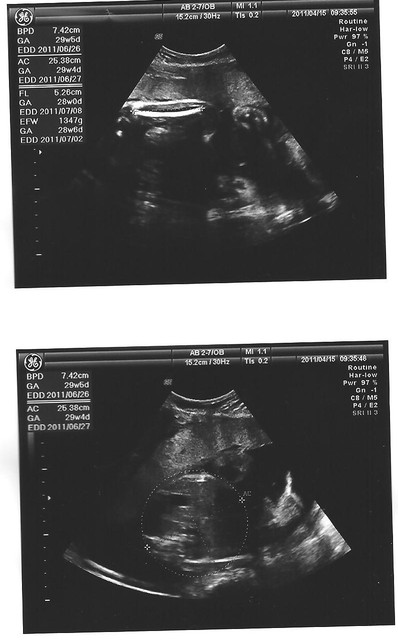

照超音波時

醫生特別幫我看了胎盤和羊水

都很正常沒異狀

二寶的體重也都有持續的增加

雖然這次感覺比sophie小隻了一點

二寶

sophie

頭圍BPD:7.42

cm (6.72cm) 頭圍BPD:

7.81cm 肚圍AC:

25.38 cm(21.54CM) 肚圍AC:23.91

CM大腿骨FL:5.26

cm(5.01CM) 大腿骨FL:5.56

CM體重EFW:1347

g(951g ) 體重EFW:1333

g